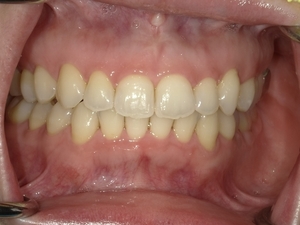

ガタガタとした歯並びや八重歯(叢生)CASE66